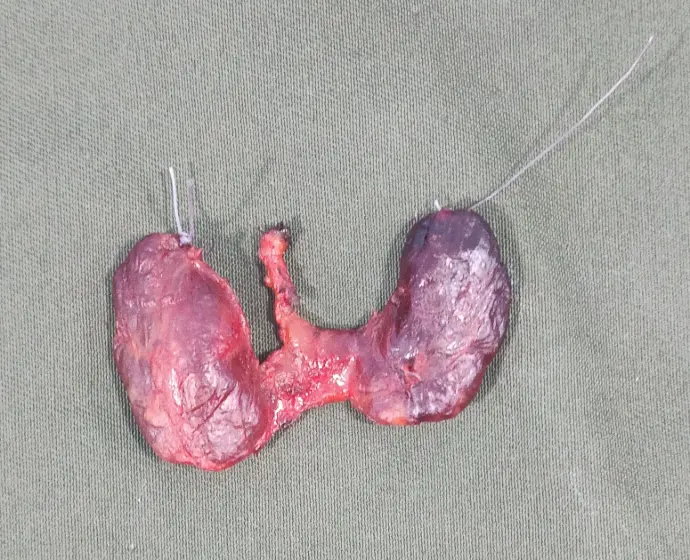

3. تضخم الغدة الدرقية (Goiter):

تضخم في حجم الغدة الدرقية.

قد يكون بسبب نقص اليود أو مشاكل أخرى مثل العقيدات الدرقية.

4. العقد الدرقية (Thyroid Nodules):

تكون كتل صغيرة داخل الغدة الدرقية.

غالبًا ما تكون حميدة، لكنها تحتاج إلى الفحص لاستبعاد السرطان.